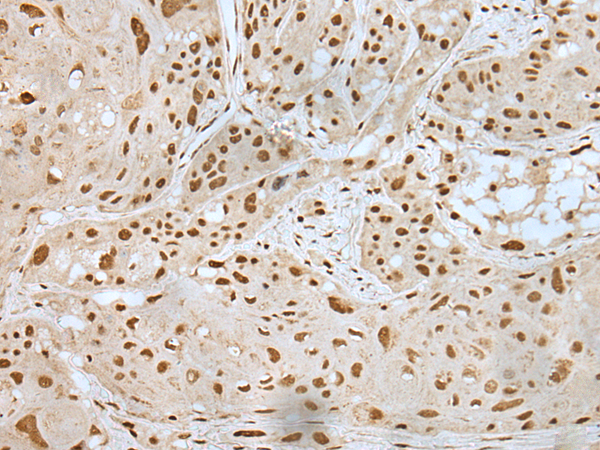

ELISA, IHC |

IHC positive control: |

Human esophagus cancer and human liver cancer |

IHC Recommend dilution: |

25-100 |